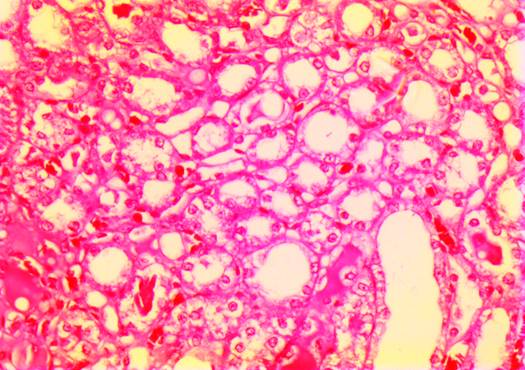

Histopathological changes in kidney

The kidney of group B rats exhibited immense necrosis of cortical tubules and glomeruli with hemorrhage Figure 1. The kidney of group C rats exposed mild necrosis of glomeruli and tubules Figure 2. The kidney of group D rats showed hemorrhage and congestion in the glomeruli Figure 3.

photo 51 kid E gum 250

Figure 1 Section of kidney of group B rats.

Figure 2 Section of kidney of group C rats

Figure 3 Section of kidney of group D rats